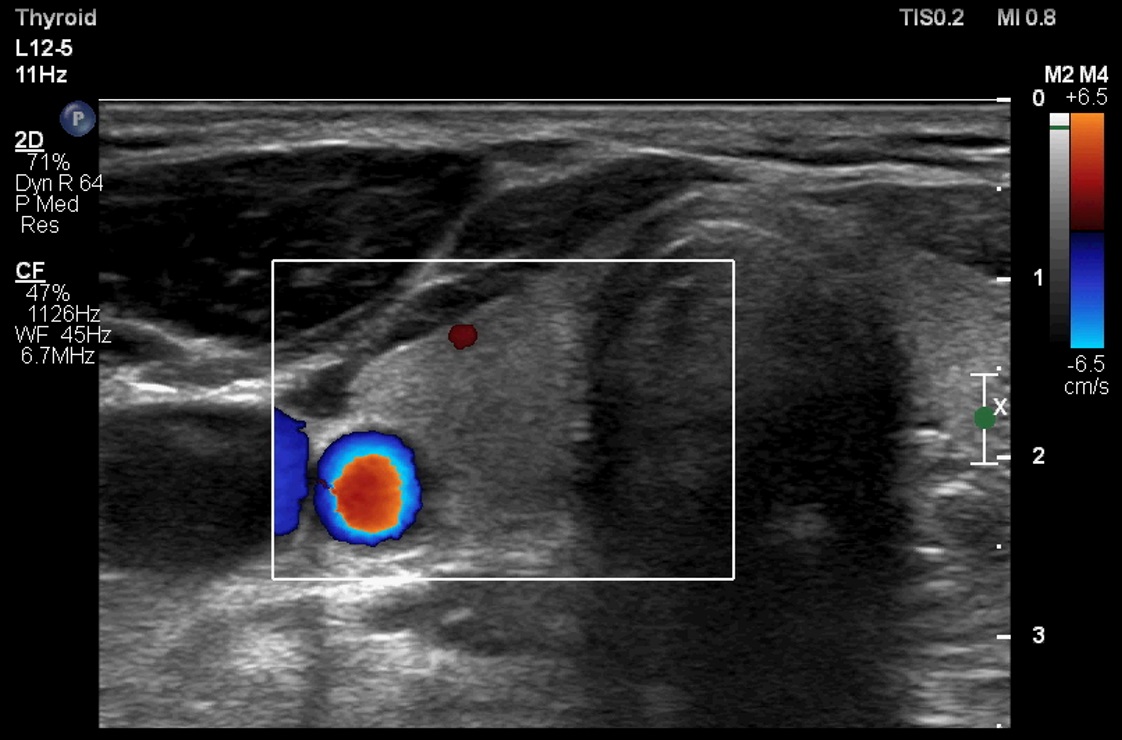

ابعاد و حجم تیروئید در سه قسمت لوب چپ (تصویر 1)، ایسم (تصویر 2) و لوب راست (تصویر 3) بررسی و معاینه میشود. همچنین سونوگرافی داپلر نیز در دو قسمت چپ (تصویر 4) و راست (تصویر 5) انجام میشود. لازم به ذکر است، همانطور که در قسمت آزمایشگاه توضیح داده شده است، هورمون TSH3 نیز به منظور غربالگری اختلالات کمکاری (کمتر از 0.01 µIU/mL) و پرکاری (بیشتر از 4 µIU/mL) انداز گیری و گزارش میشود. |